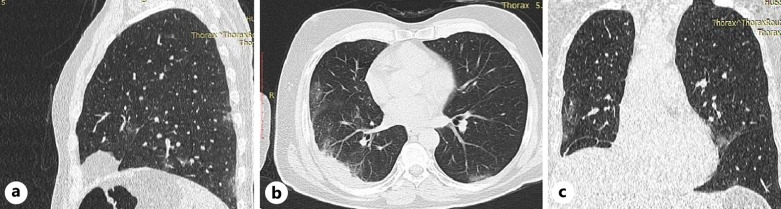

Case presentation: A 55-year-old male was presented with sudden onset of areflexic paraparesis, urinary retention, loss of all sensations below twelve spinal thoracic segments, and severe back pain. This condition necessitated an immediate order of a spinal cord MRI followed by an urgent surgery, which was crucial to save the spinal cord. COVID-19 was confirmed by a positive reverse-transcription-polymerase chain reaction and spinal MRI showed SSDH.